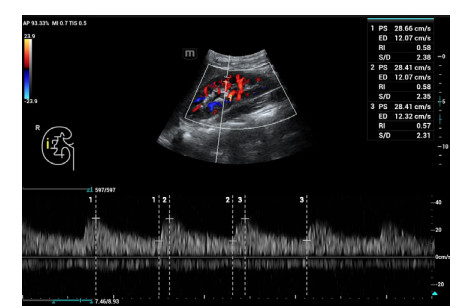

肾脏超声检查方法:所有超声检查在患者入住ICU当天由同一位超声诊断医生完成;患者取平卧位,将SC6-1s探头置于右腰部腋后线附近横切发现肾脏,再行肾脏冠状切面扫查,清晰显示上、下两极轮廓及肾内结构后启用彩色多普勒功能键显示肾脏血管并应用频谱多普勒分别于肾髓质与肾柱间检测叶间动脉(图 1)、肾窦内检测段动脉(图 2)、肾门处检测主动脉(图 3),选择3个相似且完整的频谱测量其阻力指数(resistance index, RI)值并取平均。多普勒超声检查时,声束与血流夹角尽量小于20°,取样容积在2~4 mm之间。

| 图 1 右肾叶间动脉RI值 Fig 1 The resistance index (RI) of the right renal interlobar artery |